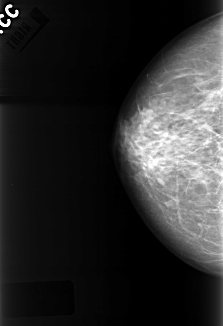

C_0325_1.RIGHT_MLO

RIGHT_CC LINES 4232 PIXELS_PER_LINE 2888 BITS_PER_PIXEL 12 RESOLUTION 50 NON_OVERLAY

RIGHT_MLO LINES 4392 PIXELS_PER_LINE 2920 BITS_PER_PIXEL 12 RESOLUTION 50 NON_OVERLAY